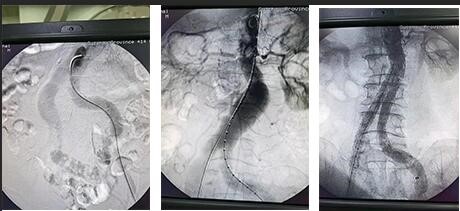

入院时赵先生病情危急,各项检查治疗必须争分夺秒进行。115日,介入科为赵先生施行腹主动脉造影+双侧髂动脉造影+腹主动脉腔内腹膜支架隔绝术+双侧髂动脉支架置入术+右侧髂内动脉栓塞术+双倒动脉内球囊扩张术。手术历时2小时,顺利完成。